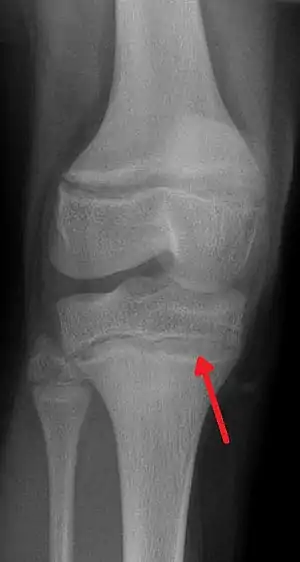

One of the clinical signs of rickets that doctors look for is cupping and fraying at the metaphyses when seen on X-ray.

The metaphysis is the neck portion of a long bone between the epiphysis and the diaphysis.[1] It contains the growth plate, the part of the bone that grows during childhood, and as it grows it ossifies near the diaphysis and the epiphyses. The metaphysis contains a diverse population of cells including mesenchymal stem cells, which give rise to bone and fat cells, as well as hematopoietic stem cells which give rise to a variety of blood cells as well as bone-destroying cells called osteoclasts. Thus the metaphysis contains a highly metabolic set of tissues including trabecular (spongy) bone, blood vessels , as well as Marrow Adipose Tissue (MAT).

During childhood, the growth plate contains the connecting cartilage enabling the bone to grow; at adulthood (between the ages of 18 and 25 years), the components of the growth plate stop growing altogether and completely ossify into solid bone.[2] In an adult, the metaphysis functions to transfer loads from weight-bearing joint surfaces to the diaphysis.[3]